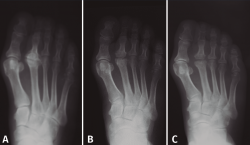

Como en todas las necrosis óseas, la radiología es característica y se corresponde con la fase evolutiva de la necrosis (Figura 3):

- Fase inicial en la que se produce la isquemia con la consiguiente muerte celular. En esta primera fase la radiología es negativa y el diagnóstico se establece con la ayuda de la gammagrafía y la resonancia magnética nuclear (RMN).

- Fase de reparación en la que existe una revascularización alrededor de la zona necrótica: vemos en la cabeza una zona más densa, que corresponde al hueso necrosado, y una zona radiolúcida alrededor de ella, que corresponde a la hiperemia.

- Fase de repercusión articular: el cartílago articular se hunde al fallarle el soporte mecánico del hueso subcondral.

- Fase artrósica en la que se ha producido la desestructuración de la articulación con pérdida del espacio articular y reacción osteofítica, tanto en la cabeza del metatarsiano como en la base de la falange.

Figura 3. Fases evolutivas de la necrosis. A: fase inicial; B: fase de reparación; C: fase de repercusión articular; D: fase artrósica.